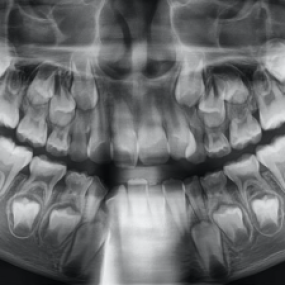

구미이튼치과 환자들의 치료후기입니다.